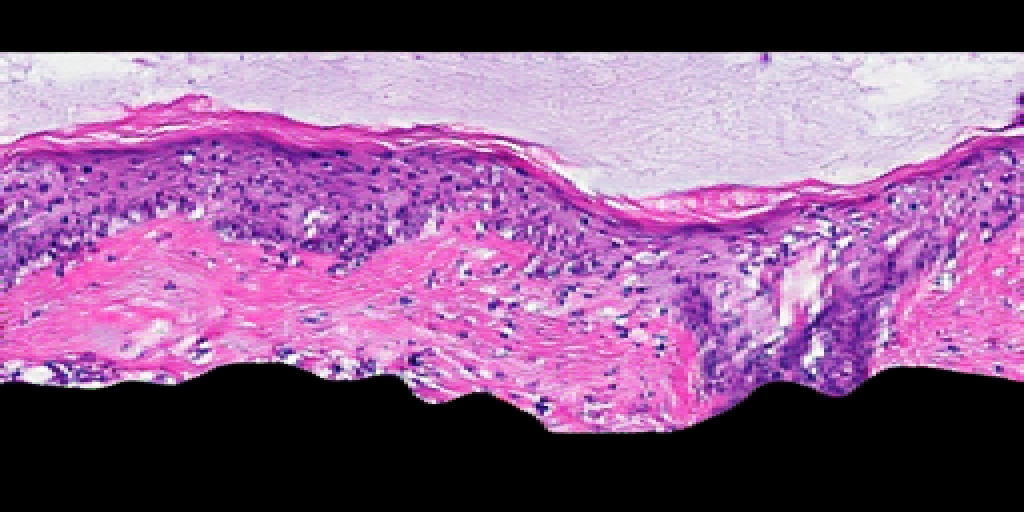

Refer to caption

Figure S1: OCT2Hist: domain transfer from OCT to virtual H&E. We show examples of an OCT image (left column), the corresponding domain transfer computer generated virtual H&E image (middle column), and the corresponding ground truth histology image (right column) from a few skin samples. Dermal epidermal junction is visible in both OCT and ground truth H&E and is reproduced by virtual H&E (arrows). Scale bar: 200 µmtimes200micrometer200\text{\,}\mathrm{\SIUnitSymbolMicro m}.